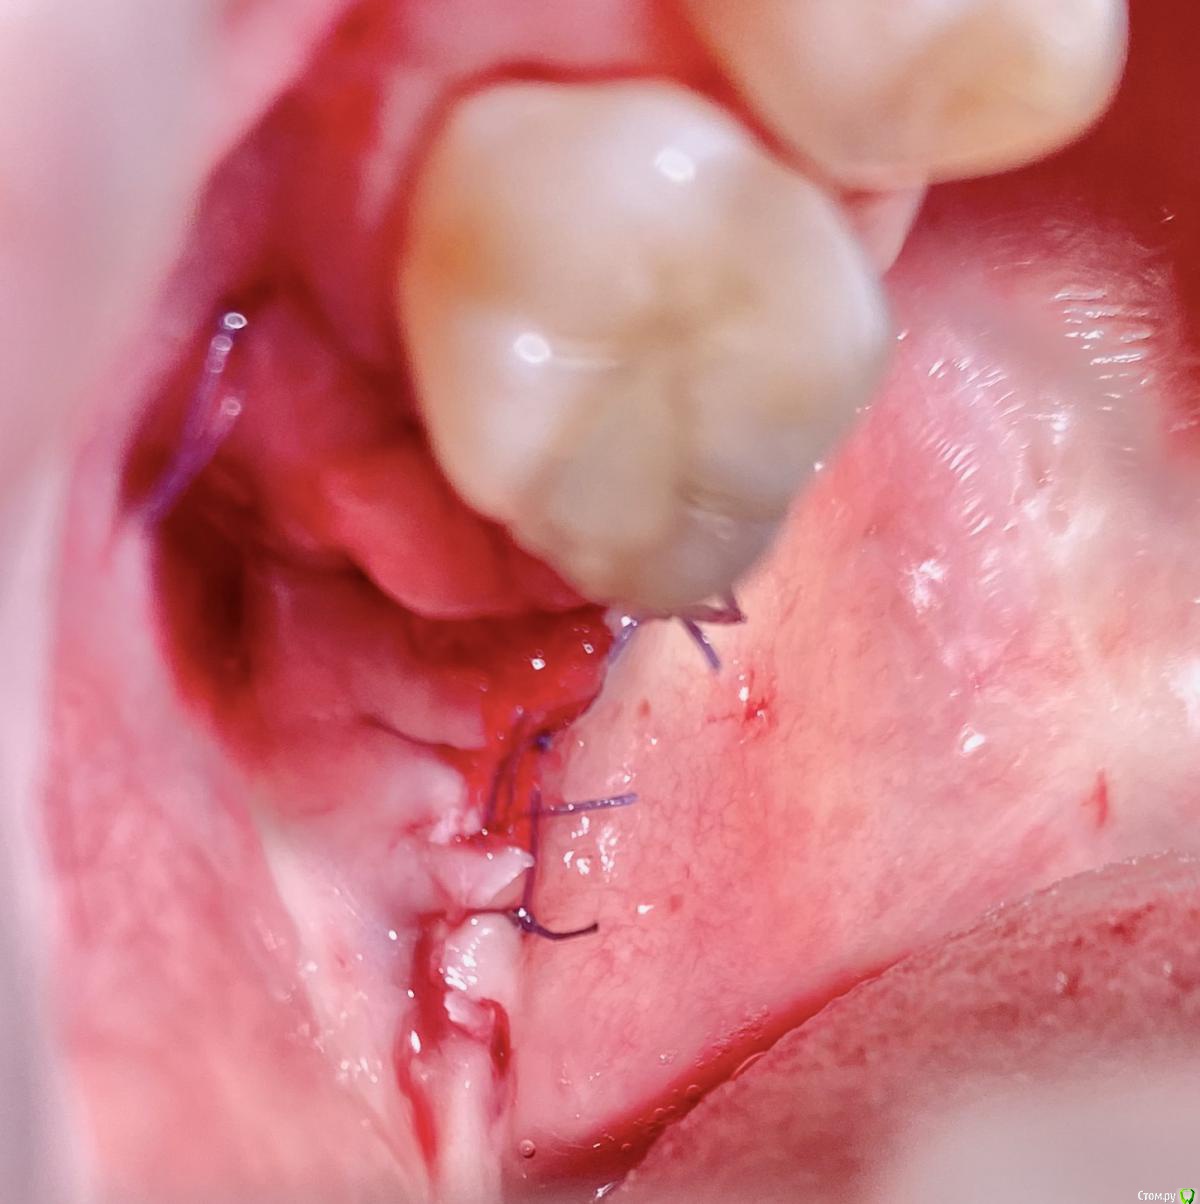

колесников Опубликовано 9 сентября, 2020 Поделиться Опубликовано 9 сентября, 2020 Т.е. на месте кривой это подслизистое отслоение, а где овал - это бугор, который нужно ротировать? овал-это бугор который мы видим и зачастую используем. Кривая-это бугор который можно забрать под слизистой. Конечно чем дальше к периферии ,тем его качество падает ,но он есть. Делаете поверхностный разрез ретромолярно,расщепляете,выделяете лоскут -заплатку,обрезаете её вестибулярно,дистально. Небно отступаете от края мм на 5 и проводите разрез до дистального края 7ки. Отделяете от основания. У вас получается заплатка на ножке. Перекидываете ее на гребень и вносите под вестибулярный край лоскута лунки,фиксируя матрасным швом. Далее придавливаете ножку перекидными швами небно-вестибулярно (ножек не прошиваем,только прижимаем). 3 Ссылка на комментарий

колесников Опубликовано 11 сентября, 2020 Поделиться Опубликовано 11 сентября, 2020 Перемещение бугра для закрытия лунки. Вестибулярно прикрепленную не смещаем. Вестибулярно компактной пластинки нет 9 Ссылка на комментарий